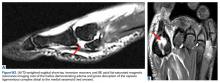

Forced hallux MTP dorsiflexion lateral view can help assess the distance from the distal sesamoid to the base of the phalanx. A small fleck of bone pulled off of the proximal phalanx or distal sesamoid may indicate a capsular avulsion or disruption. Live fluoroscopy can be very helpful in diagnosing turf toe, as the physician can assess the trailing motion of the sesamoids with increasing dorsiflexion and evaluate instability in all planes. Magnetic resonance imaging (MRI) is useful for subtle capsular injuries and can also identify osseous and articular damage that may occur and FHL disruption (Figures W2A, W2B). Nonoperative intervention focuses on rest, ice, compression, and elevation (RICE) and nonsteroidal anti-inflammatory drugs (NSAIDs). The hallux is temporarily immobilized in a plantarflexed position using a short leg cast or walking boot with toe spica or turf toe plate with tape for 2 to 3 weeks.Indications for surgical intervention include loss of push-off strength, gross MTP instability, proximal migration of the sesamoids, and progressive hallux malalignment or clawing after immobilization. Cases can involve one or a combination of the following: (1) large capsular avulsion with unstable MTP joint; (2) diastasis of bipartite sesamoid; (3) diastasis of sesamoid fracture; (4) retraction of sesamoid; (5) traumatic hallux valgus deformity; (6) vertical instability (positive Lachman test); (7) loose body in MTP joint; or (8) chondral injury in MTP joint. The goal of surgery is the restoration of anatomy in order to restore normal function of the hallux MTP joint.

The collateral ligaments are often torn away from the metatarsal head during the initial dissection and the plantar plate tear is distal to the sesamoid complex. The soft tissue defect in the plantar complex must be closed distal to the sesamoids followed by advancement of the plantar plate to the proximal phalanx in a distal to proximal fashion and advancement of the medial capsule. The plantar incision is made along the lateral border of hallux MTP-sesamoid complex just lateral to the weight-bearing surface of the hallux and the plantar lateral cutaneous nerve is carefully dissected and retracted out of the way. Sutures are placed in a figure-of-eight fashion through the plantar capsule and plantar plate starting lateral to medial to reduce injury to the nerve. If the tear cannot be primarily repaired due to inadequate healthy tissue, a plantar plate advancement can be performed directly onto the base of the proximal phalanx using drill holes or suture anchors. Proper alignment and motion of the sesamoids should be verified with fluoroscopy and compared to the contralateral hallux (Figures W3A, W3B).It is important to recognize that not all turf toe injuries involve pure hyperextension on artificial playing surfaces. In recent years, we have found an increasing rate of medial variant turf toe injuries in which a forceful valgus stress on the hallux leads to rupture of the medial collateral ligament, medial or plantar-medial capsule, and/or abductor halluces. Medial variant turf toe can lead to progressive hallux valgus and a traumatic bunion with a significant loss of push-off strength and difficulty with cutting maneuvers. Surgical treatment requires a modified McBride bunionectomy with adductor tenotomy and direct repair of the medial soft tissue defect.